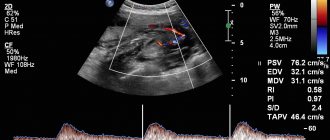

Допплерография – метод оценки кровотока плода;

Базальный ритм. Это средняя частота сердечных сокращений плода. В норме частота равна 119-159 ударов в минуту. Как урежение, так и частое сердцебиение признак того, что плод испытывает гипоксию.

Амплитуда или вариабельность. Это колебания частоты сердечных сокращений. Сокращения сердца ребенка не должны быть монотонны, и на мониторе КТГ вы можете увидеть, что цифры каждую секунду меняются. В норме колебания должны быть 5-25 ударов. Более низкая амплитуда может свидетельствовать о сне ребенка или о патологическом состоянии. Большой разбег между колебаниями говорит о патологическом состоянии плода.

Частота изменений. Этот параметр легко определить, нужно подсчитать количество зубчиков в 1 минуту. В норме 6-10 зубцов.

Акцелерации. Это учащение сердцебиения плода, которое длится от 0.5 до 1 минуты. Обычно такие увеличения базального ритма связаны с движением плода в утробе матери или с сокращением матки. Акцелерации это нормальная реакция организма, схожая с реакцией взрослого человека на физическую нагрузку. В норме за 10 минут должно быть не менее 2 таких учащений.

Децелерации. Это урежение сердцебиения плода, которое, как и акцелерации длится 30-60 секунд. Урежения являются патологическим ответом на движения плода и сокращения мышцы матки. И может свидетельствовать об обвитии пуповины или другой патологии. В норме урежений быть не должно.